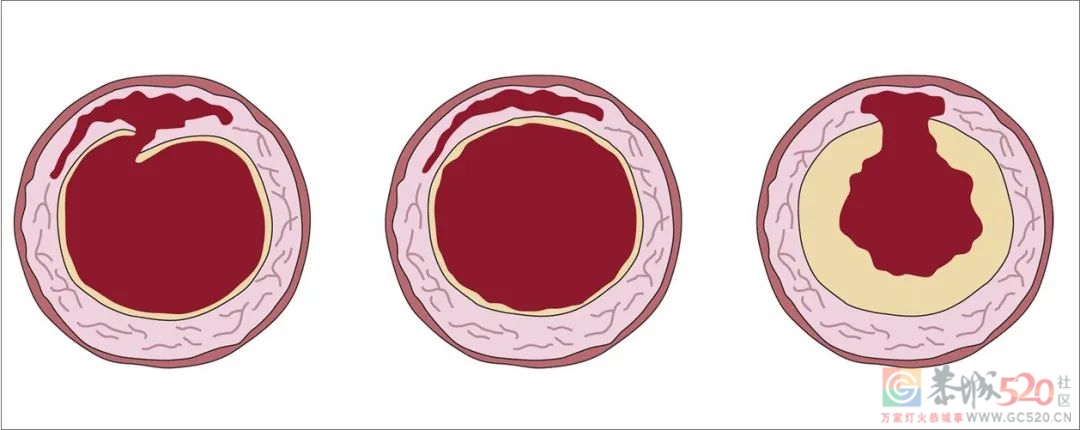

主动脉管壁有三层,分为内膜、中膜和外膜,最粗的部位直径达2.8~3厘米。如果存在高血压、动脉硬化等危险因素,血流的冲击力会把内膜撕破,血液跑到内外膜之间,就形成了主动脉夹层。通俗地说,就是血管劈了。